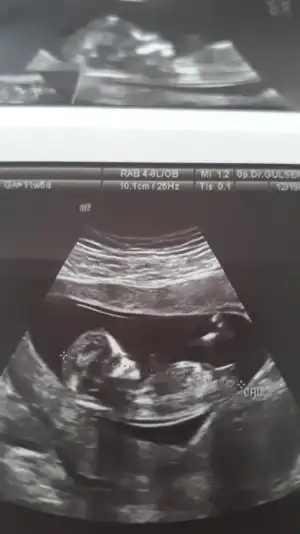

Hanımlar doktor gördü ama söylemedi sizce cinsiyetimiz nedir?

Eklentiler

• 860F41B7-BBFA-4F66-B436-18304713CDE6.webp

860F41B7-BBFA-4F66-B436-18304713CDE6.webp

19,9 KB · Görüntüleme: 50

Öğrenenler bi zahmet yazsın da bizde görelim doğru mu yanlış mi tahmin ediyoruz soran gidiyo